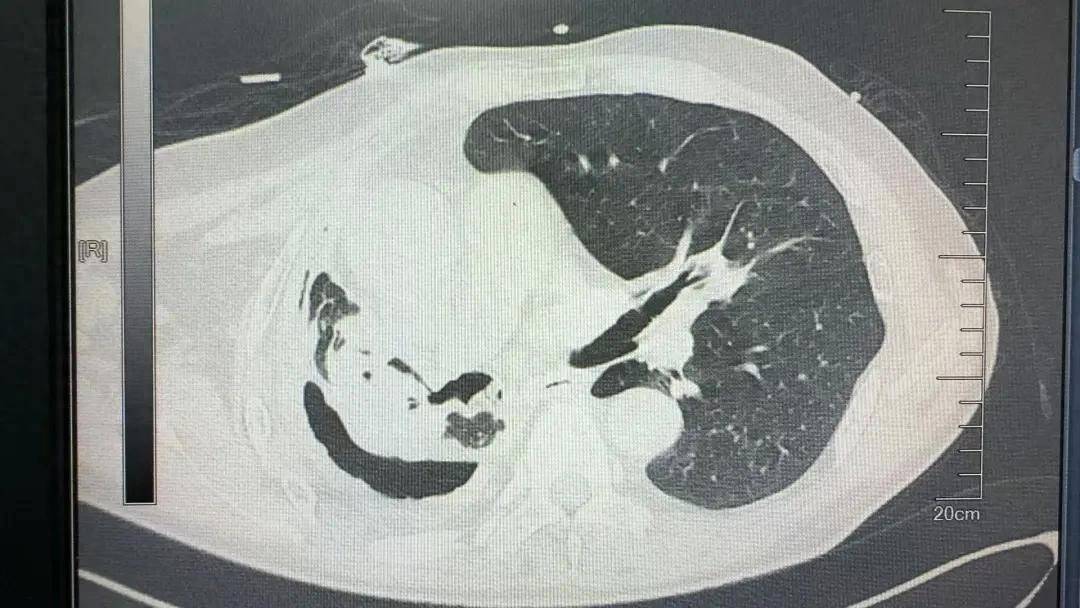

近日,河南省胸科医院胸外科九病区成功为一名53岁右侧结核性毁损肺合并主动脉瘤的高危患者实施右全肺切除手术。 持续的咳嗽、7个月的胸闷。患者老段的右肺结核菌实变毁损,已丧失功能,形成的支气管胸膜瘘和不断